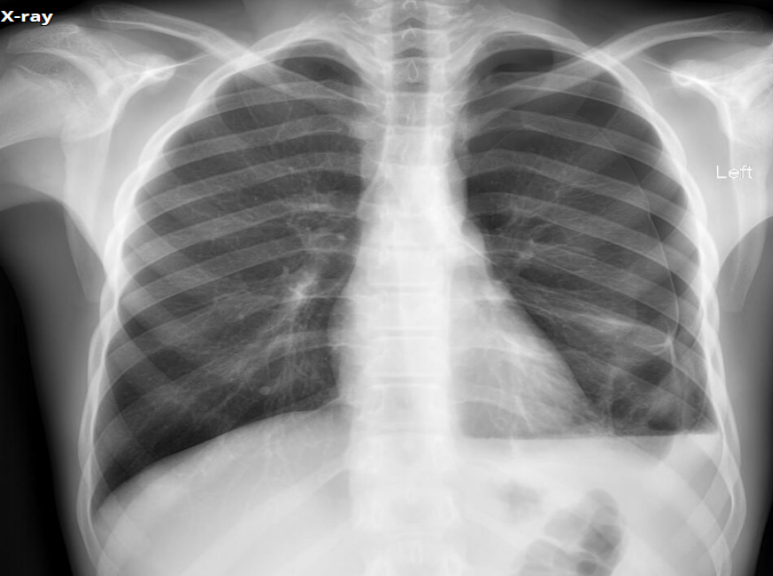

What view

PA (lower diapjragm, full lungs/large, horizontally oriented clavicales, scapula not displaced)